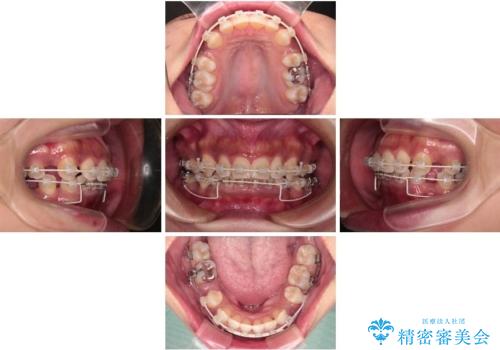

- 矯正装置

- 審美装置

「矯正装置が目立つのは避けたい」というご希望があったため、プラスチックブラケット+コーティングワイヤーを使用した審美装置を選択しました。